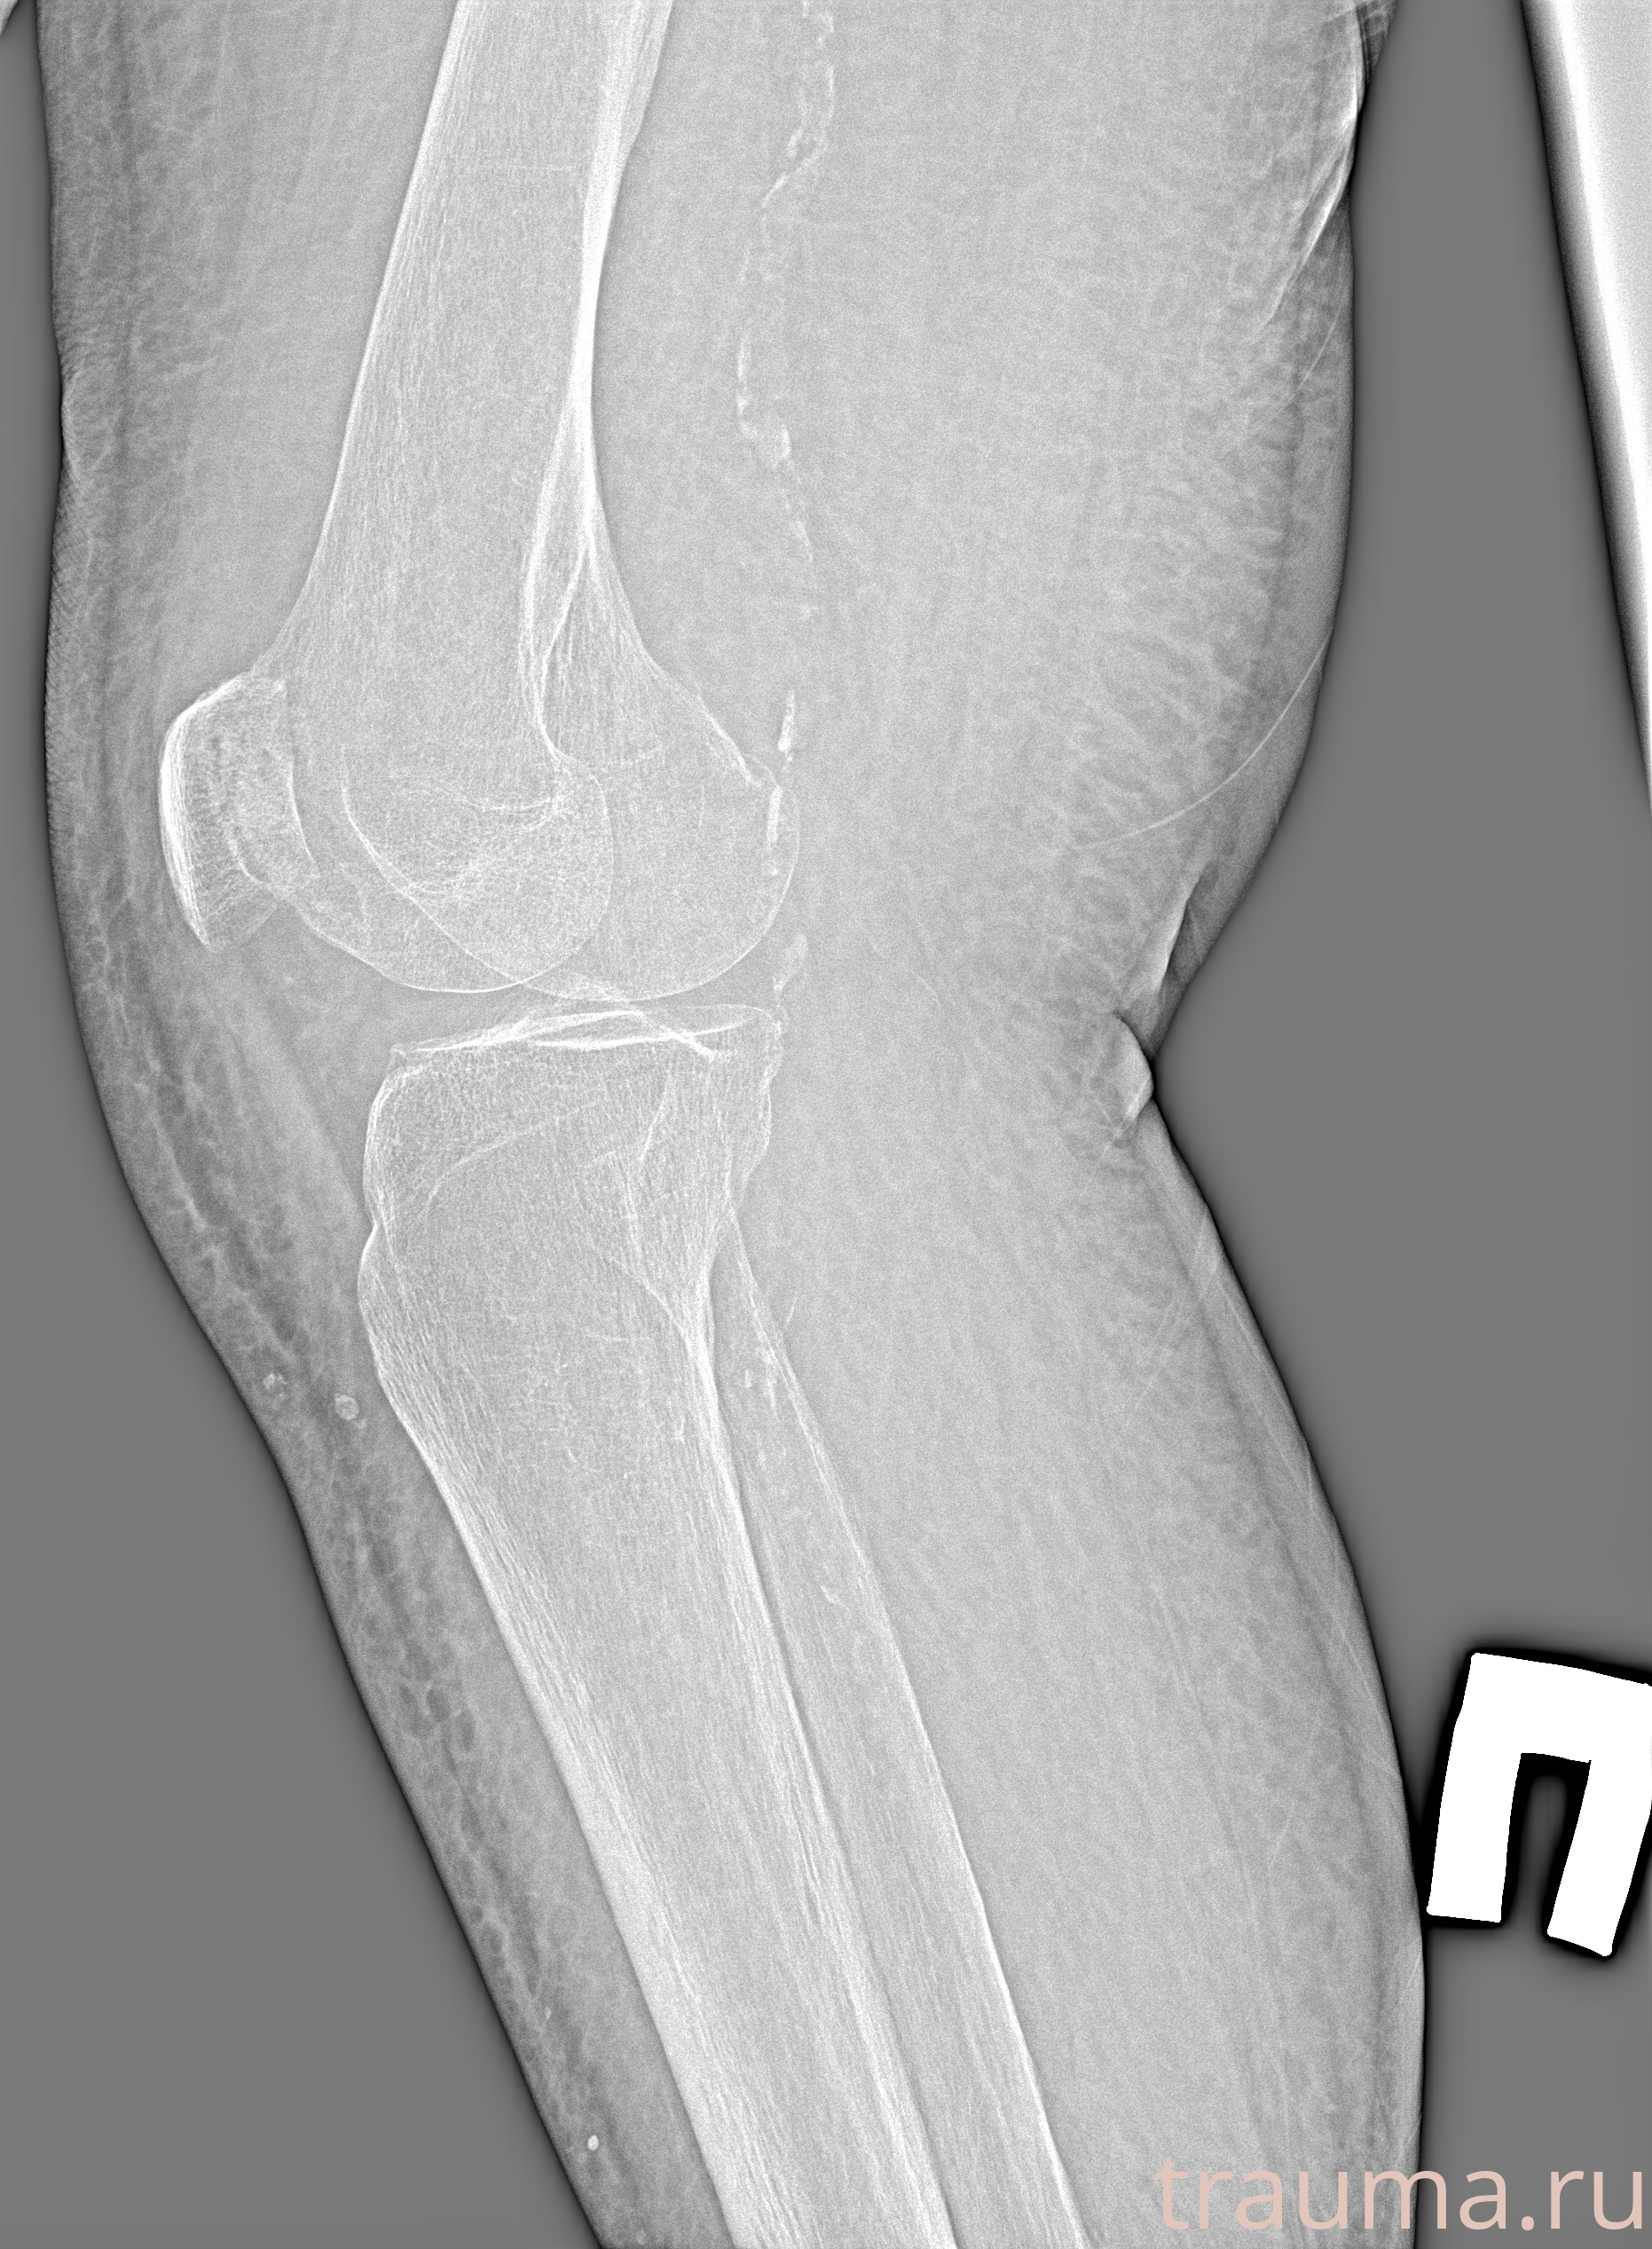

Рентген на дому: по вашему адресу приезжает врач-рентгенолог, травматолог-ортопед с мобильным рентгеновским аппаратом, проводит диагностику травмы или заболевания, делает необходимые рентгенограммы, дает рекомендации по дальнейшему лечению. Получить качественные снимки в домашних условиях возможно благодаря уникальной методике, разработанной МосРентген Центром для института  Склифосовского